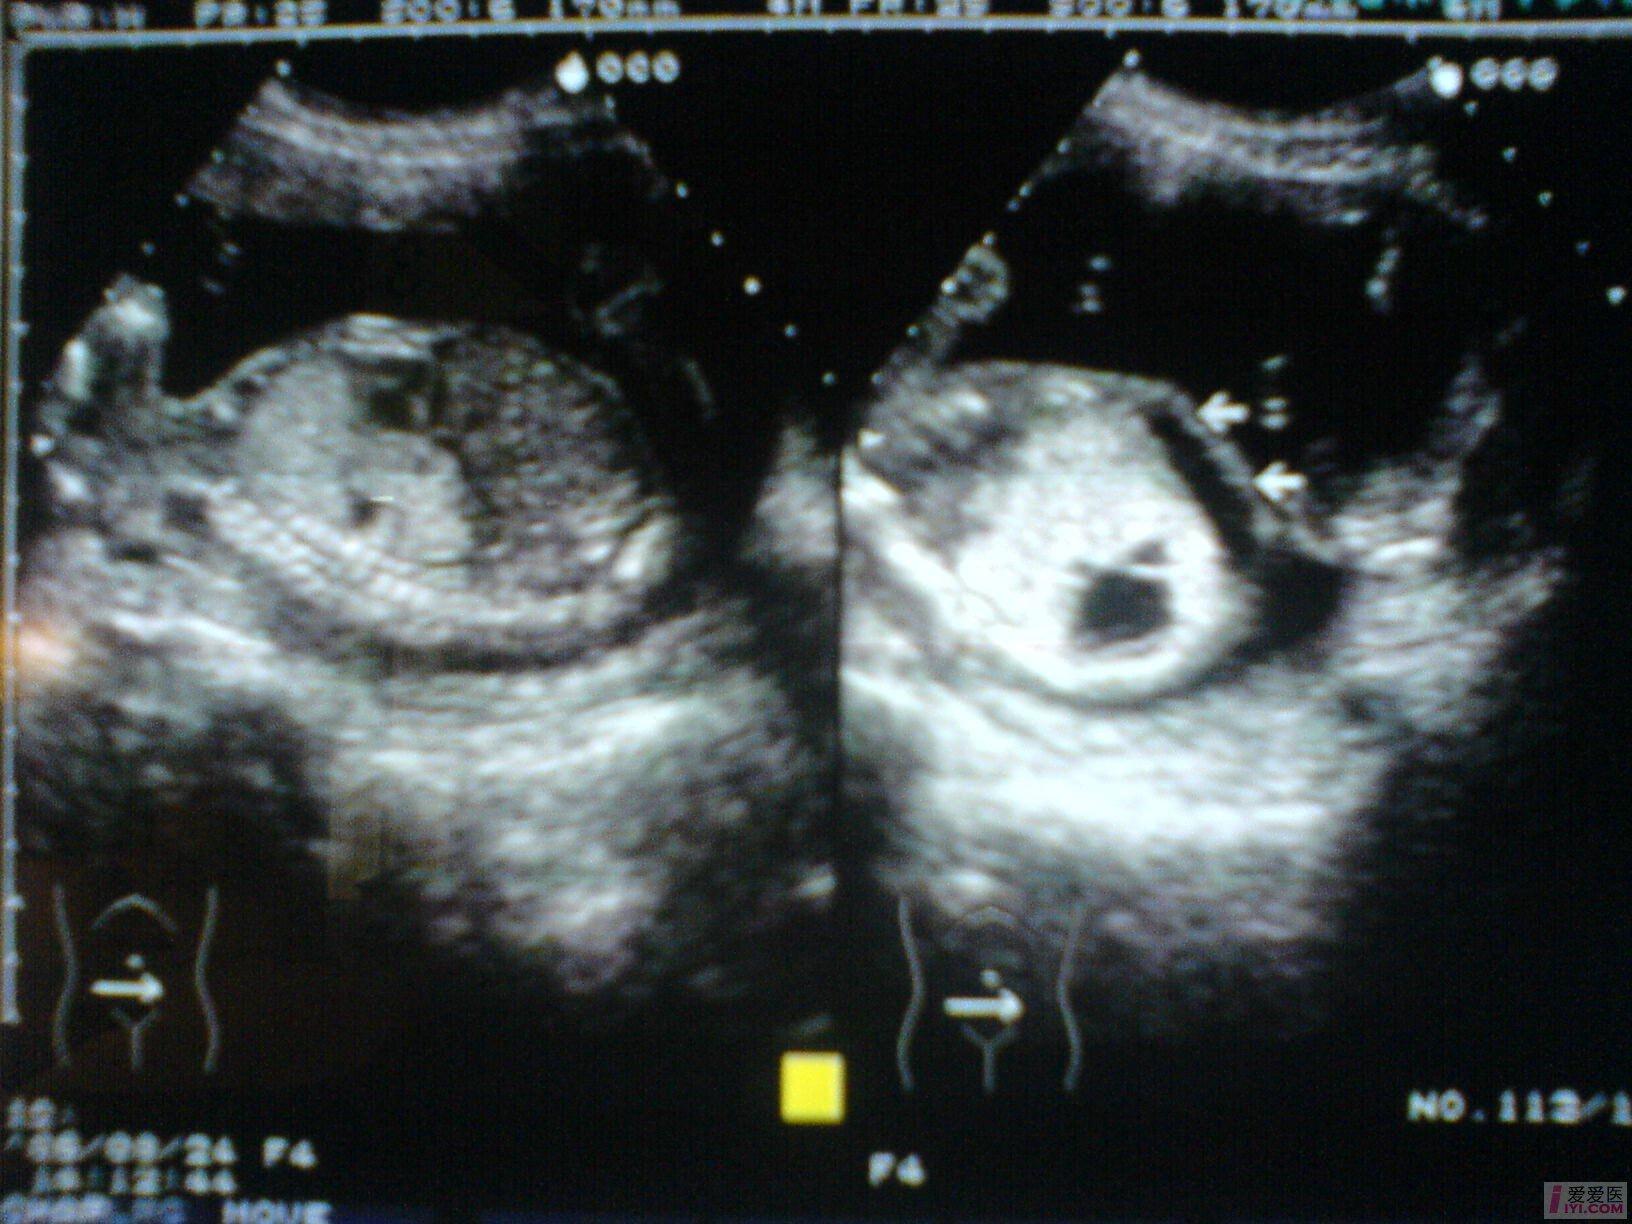

孕妇,女,33岁,G2P1,孕21周,常规产检。

B超所见:宫内单胎妊娠,胎头双顶径51mm,股骨长35mm,胎儿脊柱完整,肺实质回声增强,右侧肺叶内见31X18X17mm不规则无回声区,边界清晰,内透声好,CDFI:无回声区内未见血流信号。胎儿心胸比例失常,心脏明显受压,胎儿肝脏增大,位置下移,占据整个腹腔,回声增粗,欠均匀,未见胃泡回声,肝脏周围见宽4mm无回声暗区。胎动活跃,胎心搏动好,胎心律150bpm,胎盘附于前壁,厚21mm,回声均匀,最大羊水暗区深度74mm,透声好。

B超提示:1.宫内中孕,单胎存活,胎儿发育符合21周。

2.胎儿肺实质回声增强,右侧肺叶囊性占位,肝大,少量腹水。

请教:该例病例可否考虑胎儿肺囊腺瘤样变? [readperm]1[readperm]